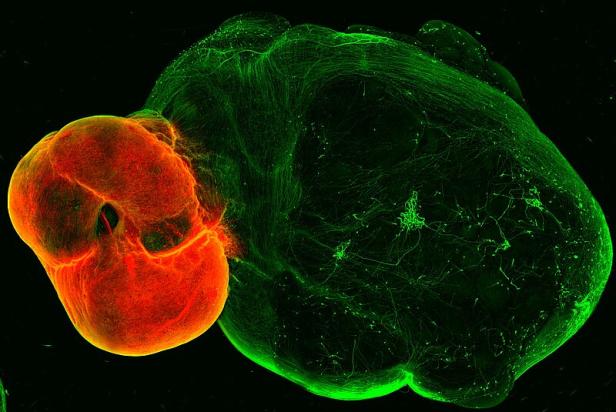

Ein Beispiel sind Gehirnorganoide aus menschlichen Stammzellen, dreidimensionale Gewebe-Modelle des Gehirns in einem sehr frühen Stadium. „Die Zellen ordnen sich in Selbstorganisation so an wie in einem wirklichen menschlichen Gehirn.“ Damit habe man jetzt ein Testsystem für neue Therapien.

An diesem speziellen Gehirn-Organoid können Therapien gegen Parkinson getestet werden.

Knobloch und Daniel Reumann haben ein Gehirn-Organoid entwickelt, an dem man Therapien gegen Parkinson testen kann. Bei Parkinson gehen im Mittelhirn jene Nervenzellen zugrunde, die für die Produktion des Botenstoffs Dopamin zuständig sind. In Japan und den USA wurden ersten wenigen Parkinson-Patienten in kleinen Pilotstudien Vorläuferzellen dieser Nervenzellen ins Gehirn injiziert.

Das Team um Knobloch konnte in Kooperation mit der Universität Lund (Schweden) zeigen, dass in ihrem speziellen Gehirnorganoid solche Vorläuferzellen tatsächlich zu vollständigen Nervenzellen heranreifen.